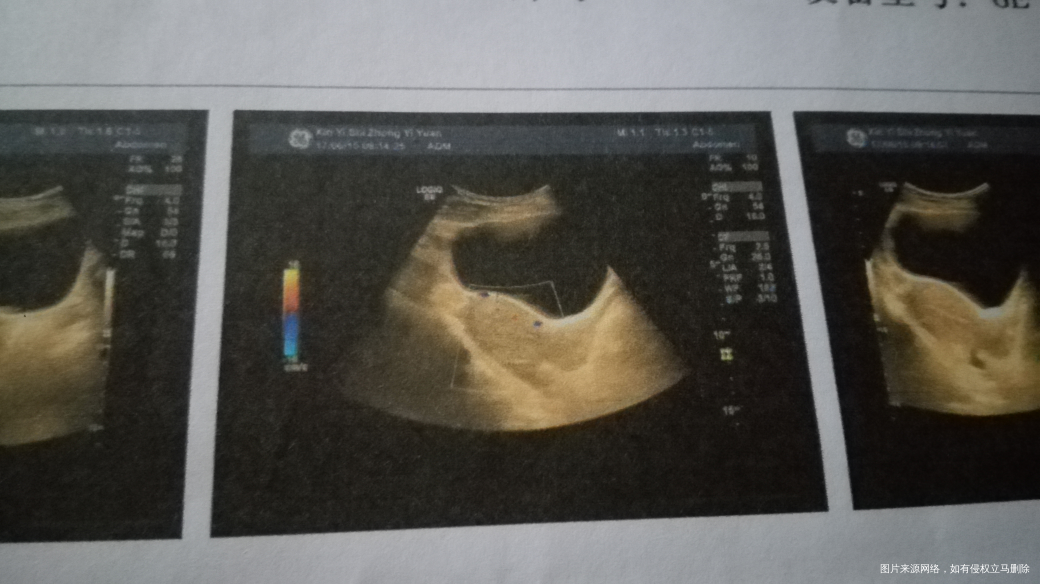

这是今天的B超单,我是6月5号清的宫,今日还有少少血,还有我的内膜正常吗,是不是很薄,需要吃补佳乐补内膜

吗?

您好,看您的产生报告没有异常的

你好,内膜厚度正常,如果出血不多再观察